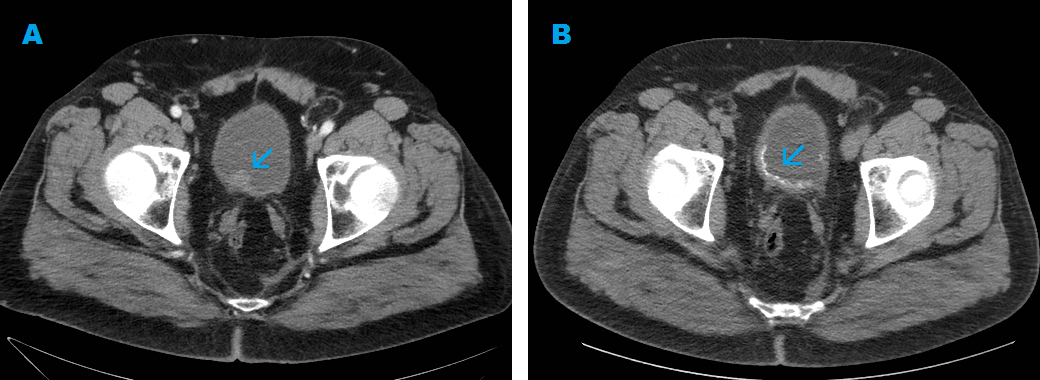

Our patient was a 65-year-old man who had ultra-low anterior resection and chemo-radiotherapy for rectal cancer. On follow-up computed tomography (CT) scan of the abdomen and pelvis a year later, he was found to have a bladder mass (Fig. 1). He subsequently underwent elective TURBT and received intravesical mitomycin C (40 mg diluted in 40 ml of saline 0.9%) within 6 h post-operatively. Histology revealed non-invasive, low-grade TCC. Three weeks later, a follow-up CT scan of the abdomen and pelvis was performed for routine follow-up of the rectal cancer; this scan incidentally detected calcification of the bladder wall at the surgical resection site (Fig. 1). He was asymptomatic. Cystoscopy and cystolitholapaxy was then performed for presumed bladder calculi, approximately three months after the TURBT. Extensive stone-like, whitish calcification of the bladder wall at the surgical resection site was found (Fig. 2), not merely slough or soft tissue material. These lesions were further resected down to the detrusor muscle layer as the material was not amenable to washout. Histology (Fig. 3) revealed chronic inflammation of urothelium and fragments of refractile, hard-edged material which was found to be made up of calcium phosphate. There were no features of malignancy. He had normal serum calcium and phosphate levels and no known history of exposure to tuberculosis or schistosomiasis or travel to Africa, Middle East or South East Asia. He had no symptoms of interstitial cystitis. Aside from the history of rectal cancer and associated therapy, he had no other relevant oncological history. He received intravenous fluorouracil, folinic acid and oxaliplatin adjuvant chemotherapy for rectal cancer with the final cycle administered more than 12 months prior to this diagnosis of bladder wall calcification. He never received any intravesical therapy prior to the single dose of mitomycin C administered after the initial TURBT. In view of the rapid onset and localized involvement of the resection site, the bladder wall calcification was most likely secondary to intravesical mitomycin C treatment. Since this episode, there was no further recurrence or long-term consequence. Thus, no further treatment was required aside from routine cystoscopy for follow-up of non-muscle invasive, low-grade bladder cancer.

Figure 2. Cystoscopy revealed extensive whitish calcification of the bladder wall, especially at the previous surgical resection site.